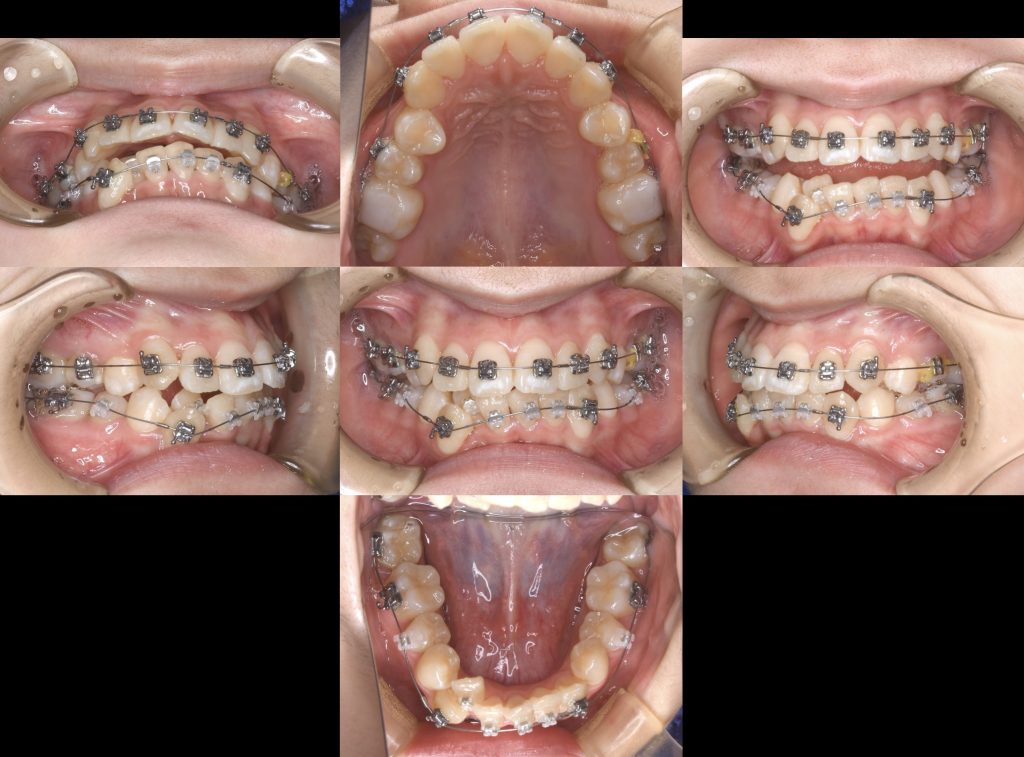

下記の症例は歯列不正(叢生)に対して、第一小臼歯を上下4本抜歯し、スペースクローズをワイヤー矯正にて行いました。

治療期間 2年6ヶ月

治療費用 約140万円(税抜き)